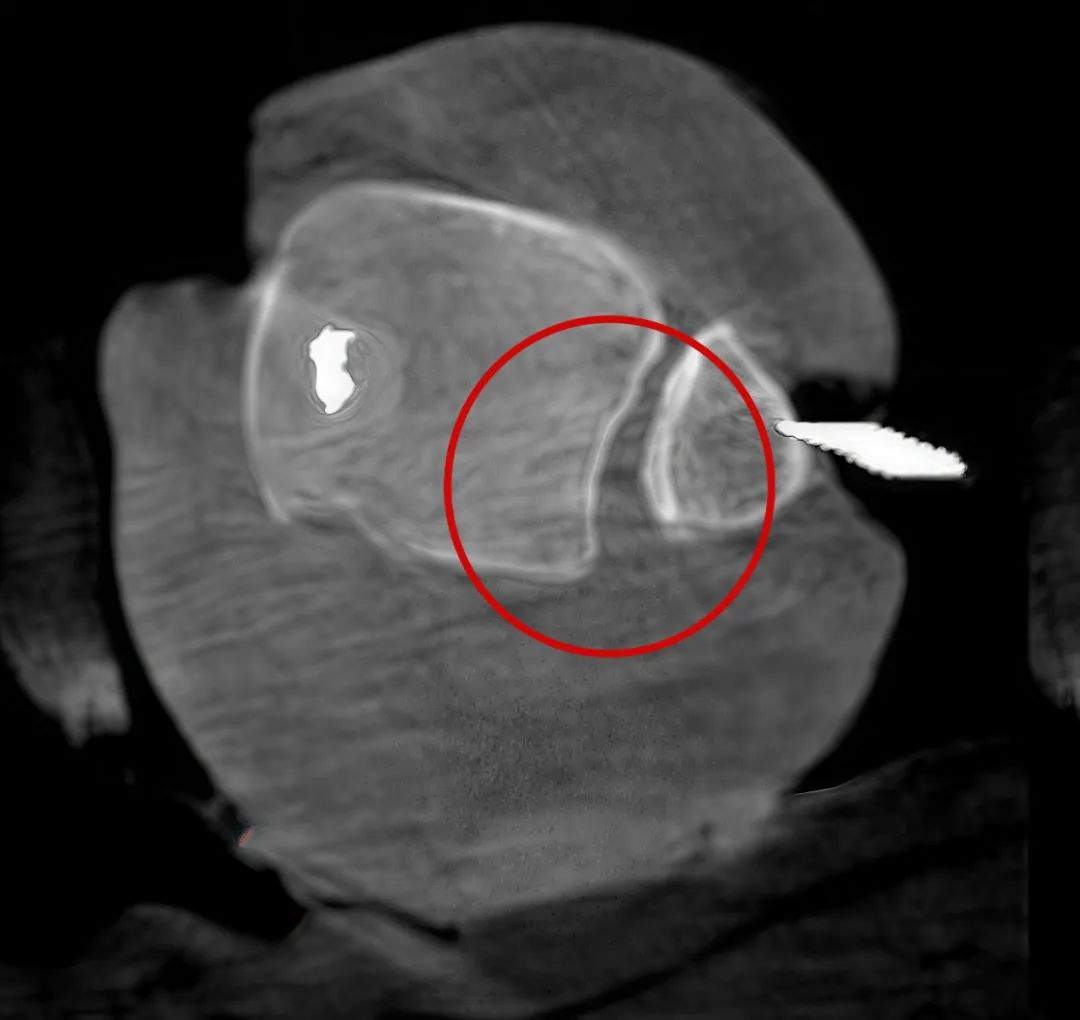

三維C形臂圖像

從三維影像看,復位欠佳,貼合度不夠